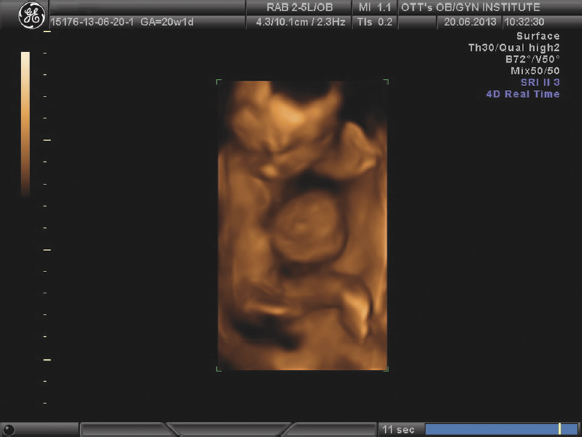

Рис. 1. Хейлогнатопалатосхизис, 20 недель беременности

Рис. 2. Редукция правой кисти плода, 17 недель беременности

Преобладающее большинство особенностей развития было выявлено в первой половине беременности (до 80 %), причем 30 % из них — в I триместре (табл. 2). За период с 2013 по 2017 г. наметилась тенденция к увеличению числа пороков развития, обнаруженных в I триместре. За исследуемый период значительно выросла частота выявления в I триместре таких пороков, как хейлогнатопалатосхизис, полидактилии, редукционные пороки конечностей (рис. 1, 2). По нашему мнению, значительно увеличить процент диагностики пороков развития возможно при более раннем обращении (I триместр) в учреждения экспертного уровня.